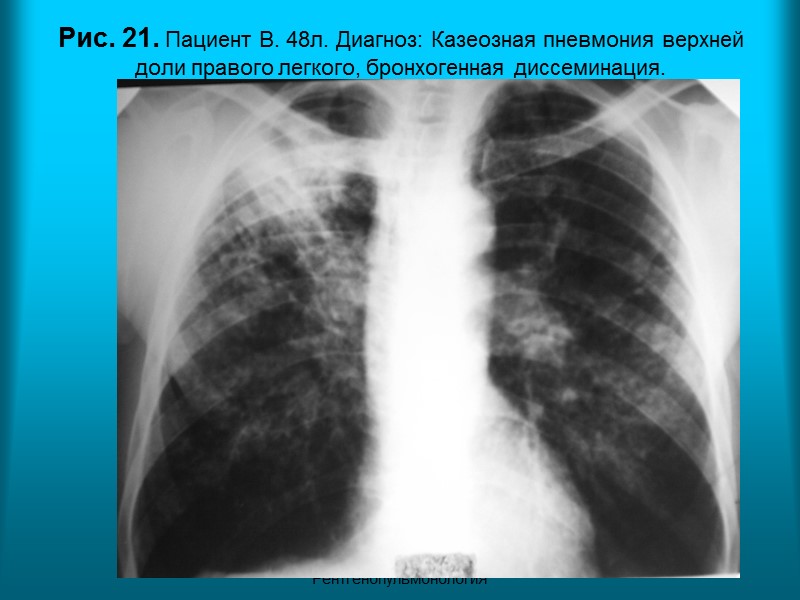

Н.С. Воротынцева. С.С. Гольев Рентгенопульмонология Рис. 21. Пациент В. 48л. Диагноз: Казеозная пневмония верхней доли правого легкого, бронхогенная диссеминация.